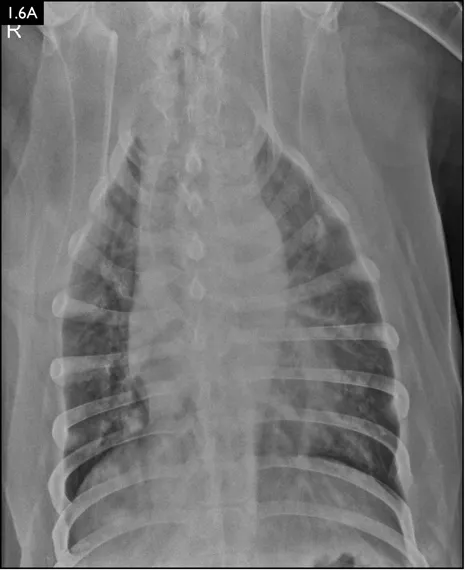

Clinical signs can be strongly suggestive of bacterial pneumonia, but radiographs are important for confirmation, to characterize the disease (and potential etiology) and to provide a baseline for monitoring response to treatment (Figs. 1.4–1.6). A lag between clinical signs and radiographic changes can occur, and initial radiographs may be normal or appear discordant with clinical severity.

Fig. 1.4A–D Lateral and ventrodorsal radiographs of a dog with doxycycline-responsive pneumonia of unknown etiology before treatment ( A, B) and six days later ( C, D). Note the severe multilobar alveolar pattern that was present initially, most prominently in the left cranial lung lobe. (Courtesy of Atlantic Veterinary College)